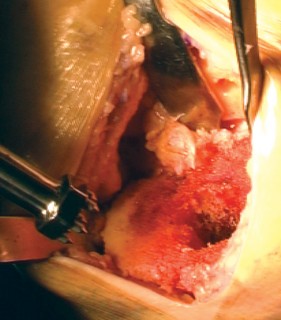

خطوات العملية الجراحية بالتفصيل

الخطوة 1: التحضير الأولي والوصول إلى المفصل

-

الوصول إلى المفصل (الشقوق):

يستخدم الأستاذ الدكتور محمد هطيف عادةً نهجًا جراحيًا طفيف التوغل (abbreviated trivector approach) للوصول إلى الركبة.

- يتم عمل شق جراحي يبدأ من الجزء الإنسي للحدبة الظنبوبية ويمتد إلى الجزء العلوي من الرضفة.

- يتم فصل ارتباط العضلة المتسعة الإنسية عن وتر العضلة الرباعية، مع الحرص على عدم تجاوز 3 سم فوق القطب العلوي للرضفة.

- يتم رفع غشاء الأنسجة الرخوة الإنسي بعناية وصولاً إلى الزاوية الخلفية الإنسية للركبة.

- يتم إزالة جزء من الوسادة الدهنية للرضفة.

- تُدفع الرضفة بعد ذلك إلى الميزاب الجانبي وتُثنى الركبة لزيادة كشف المفصل.

مفاتيح النجاح الجراحي (Pearls):

- رفع الرباط الجانبي الإنسي (MCL) بعناية يمنع تمزقه عند تحريك الركبة.

- توسيع الشق الجراحي تدريجيًا عند الحاجة يوفر رؤية أفضل في الحالات الصعبة.

الخطوة 2: قطع عظم الفخذ (Femoral Cuts)

- الدليل داخل النخاع (Intramedullary Guide): يُستخدم دليل داخل النخاع لعظم الفخذ لضمان دقة القطع.

- ثقب كبير: يُحدث ثقب كبير في الجزء الأوسط من الشق بين اللقمتين.

- تحديد الزاوية: يُضبط الدليل داخل النخاع بزاوية 4 درجات ويُدخل في قناة الفخذ. يتم تركيب قالب القطع الفخذي البعيد (distal femoral cutting block) على الدليل.

- التثبيت والقطع: يُثبت القالب في مكانه ويُقطع الجزء البعيد من عظم الفخذ.